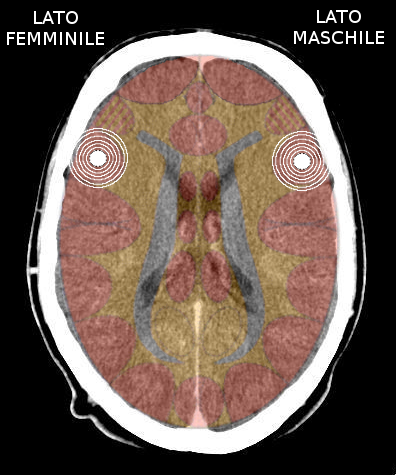

- Insula destra = ormonalità, percettività e comportamento maschile, sia nella femmina che nel maschio, destrimane o mancino. Quando attivata causa tonalità depressiva;

- Insula sinistra = ormonalità, percettività e comportamento femminile, sia nella femmina che nel maschio, destrimane o mancino. Quando attivata causa tonalità maniacale.

Quando si attiva la corteccia insulare dominante della persona, questa si chiude ad altri SBS territoriali. Se avviene una nuova attivazione territoriale, senza che la prima si sia risolta, verrà coinvolta la corteccia insulare controlaterale e la persona entra in Costellazione.

È importante considerare l'intensità dei due conflitti.

- Se quello a destra è il più "pesante", la persona è tendenzialmente depressa;

- Se quello a sinistra è il più "pesante", la persona è tendenzialmente maniacale;

- L'alternanza sui due lobi temporali, determinata dalla quotidianità della persona, causa il bipolarismo.